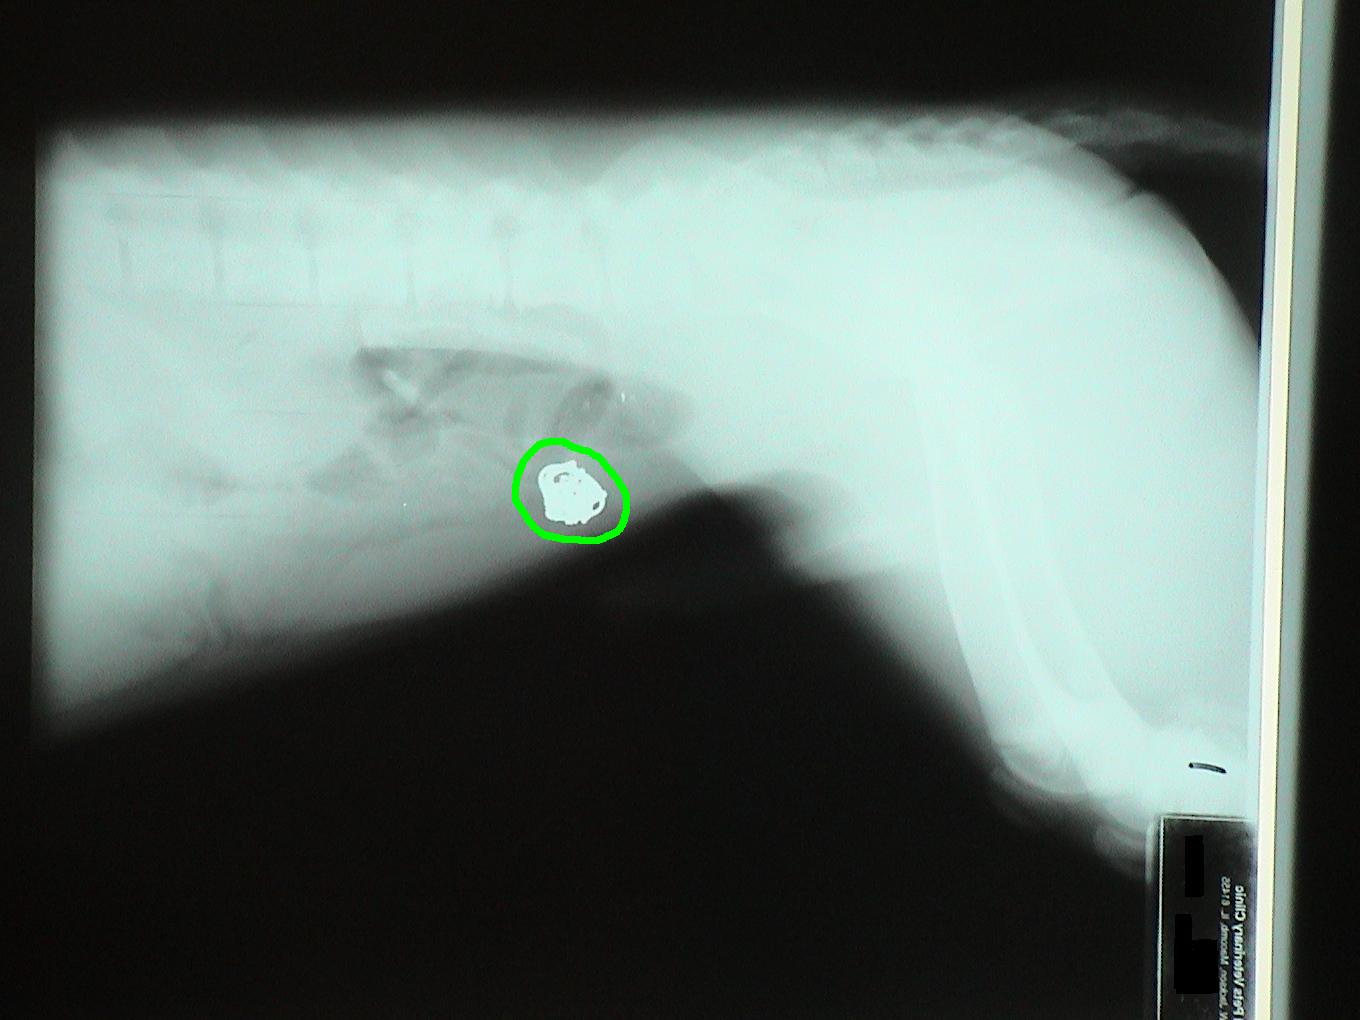

Let's identify the foreign bodies in each of these x-rays.